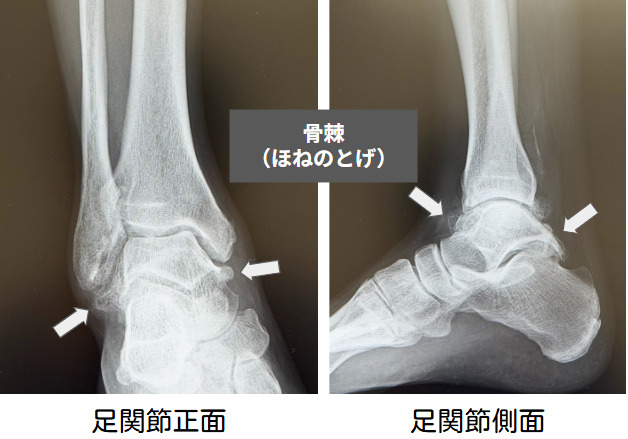

まずは捻挫や骨折などの外傷がないかを問診します。レントゲン検査で診断は容易で、関節裂隙の狭小化、骨棘形成、骨嚢胞など関節の変形に伴う様々な変化を認めます。本邦では高倉・田中分類(Takakura/Tanaka Classification)が用いられ、Stage1-4に分けられます。X線検査による分類のみで治療法が決定するわけではないことに注意が必要です。

前方インピンジメントが主病変である症例では、関節鏡下デブリードマンや外骨腫切除術が関節温存術として有効で、脛骨前方骨棘による疼痛に対して良好な成績が期待できます。ただし、進行した足関節症に対する有効性を支持する十分な根拠は限られています。軽度から中等度の関節症で、脛距関節のマルアライメントや偏心性摩耗を伴う場合には顆上骨切り術が適応となり、術前の距骨傾斜角は成績に大きく影響します。